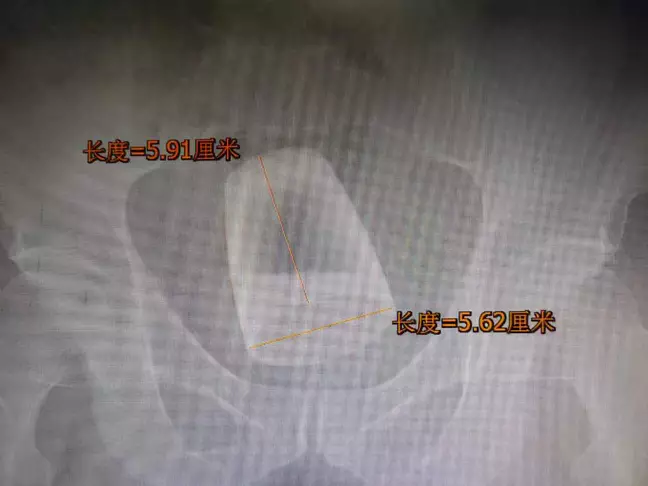

According to a report from the hospital, the glass was 6cm tall with a diameter of 5.6cm.

X-ray images show how the beer glass was positioned around 2.36 inches (6 centimeters) up the patient’s rectum.